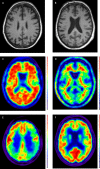

Case showing clinical use of biomarkers. A 56 year old patient presented with a 5–10-year history of ‘scattiness’. Three years ago she developed difficulties reading an analogue clock, her spelling had declined and she had difficulty reading, losing her place from line to line. She received a clinical diagnosis of posterior cortical atrophy. Subsequently episodic memory became impaired. At the time of scanning, the Mini-Mental State Examination score was 19/30. A T1 volumetric MRI of the brain demonstrated a posterior pattern of cortical atrophy (A) with preserved hippocampal volumes compared with a healthy control patient (B); A 18F-florbetpair amyloid positron emission tomography (PET) scans shows widespread cortical amyloid deposition (C) compared with a healthy control (D) fludeoxyglucose (18F) PET scan demonstrates a posterior dominant pattern of hypometabolism (E) SUVR 1.0–1.4, compared with an age matched healthy control (F) SUVR 1.0–1.5. Cerebrospinal fluid examination demonstrated an elevated t-tau: 1080 pg/mL (NR 146–595); Aβ1–42 360 pg/mL ((NR 627–1322) giving a tau/Aβ1–42 ratio of 3. This case illustrates how different biomarkers can provide complementary information including regional neuronal loss, more widespread metabolic dysfunction, as well as confirming the underlying pathology—in this case, Alzheimer's disease. (NB for clinical purposes, 18F-florbetapir images should be interpreted on a grey rather than colour scale.)